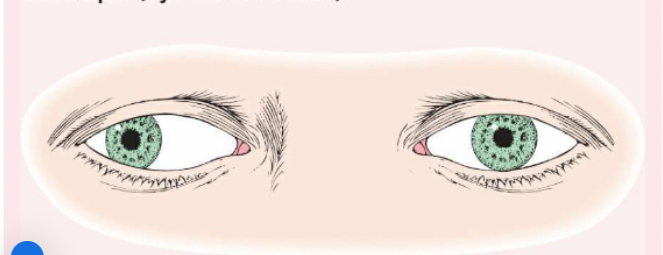

Pseudostrabismus

Normal in young children, the pupils will appear at the inner canthus (due to the epicanthic fold).